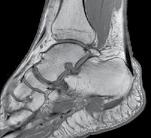

Diagnostic clinic

Suspiciunea clinică de fractură platou tibial este dată de prezența durerii la nivelul genunchiului, asociată cu impotență funcțională, tumefacție locală, însoțite de un istoric sugestiv de mecanism traumatic.

rențial. Se pot decela flictene sau prezența unei fracturi deschise.

O tumefacție marcată poate necesita puncție evacuatorie cu evidențierea hemartrozei. Apariția urmelor de grăsime este sugestivă pentru o fractură intraarticulară.

Toate compartimentele musculare ale gambei trebuie palpate. Prezența presiunii crescute ridică suspiciunea unui sindrom de compartiment. Presiunea crescută poate fi cuantificată prin măsurarea acesteia intracompartimental.

Pacienții politraumatizați, cu multiple leziuni, vor fi evaluați multidisciplinar, urmând protocolul ATLS. Se va identifica leziunea prioritară, amenințătoare de viață, conform conduitei terapeutice A, B, C, D și se va institui tratament specific în vederea stabilizării bolnavului. Lipsa pulsului distal la un membru pelvin poate constitui urgență ortopedică.

Se practică examinarea clinică minuțioasă a întregului genunchi, comparativ cu cel controlateral, prezumtiv sănătos, acordând multă atenție următoarelor elemente.

Tegumentul se inspectează circumfe-

Se practică teste de laxitate. O laxitate mai mare de 10 grade la nivelul interliniumului articular, la un test de varus, valgus forțat, sugerează o leziune de colateral. Prezența acesteia sub interlinium este caracteristică fracturii.

Mobilitatea activă și pasivă a genunchiului este dificil de examinat datorită durerii intense, caracteristice fazei acute.

Diagnostic imagistic

Articulația genunchiului trebuie sistematic examinată în vederea decelării

Se practică radiografii standard, examinare CT sau RMN.

Radiografiile se fac în cel puțin 3 incidențe: antero-posterioară, laterală și notch intercondilar.